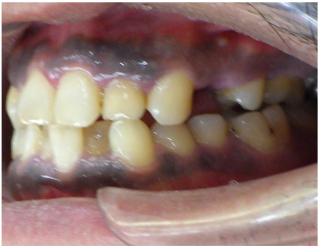

この方は前歯の歯並びと奥歯の虫歯、欠損の治療を希望されました。

前歯の歯並びはセラミック法で治療しました。

奥歯の欠損はブリッジで治療しました。

また、下の前歯も歯周病で1本抜歯になりましたのでその部分もブリッジ治療しています。

当院ではこの様にいろいろな歯のお悩みがあっても同時進行で治療する事が可能です。